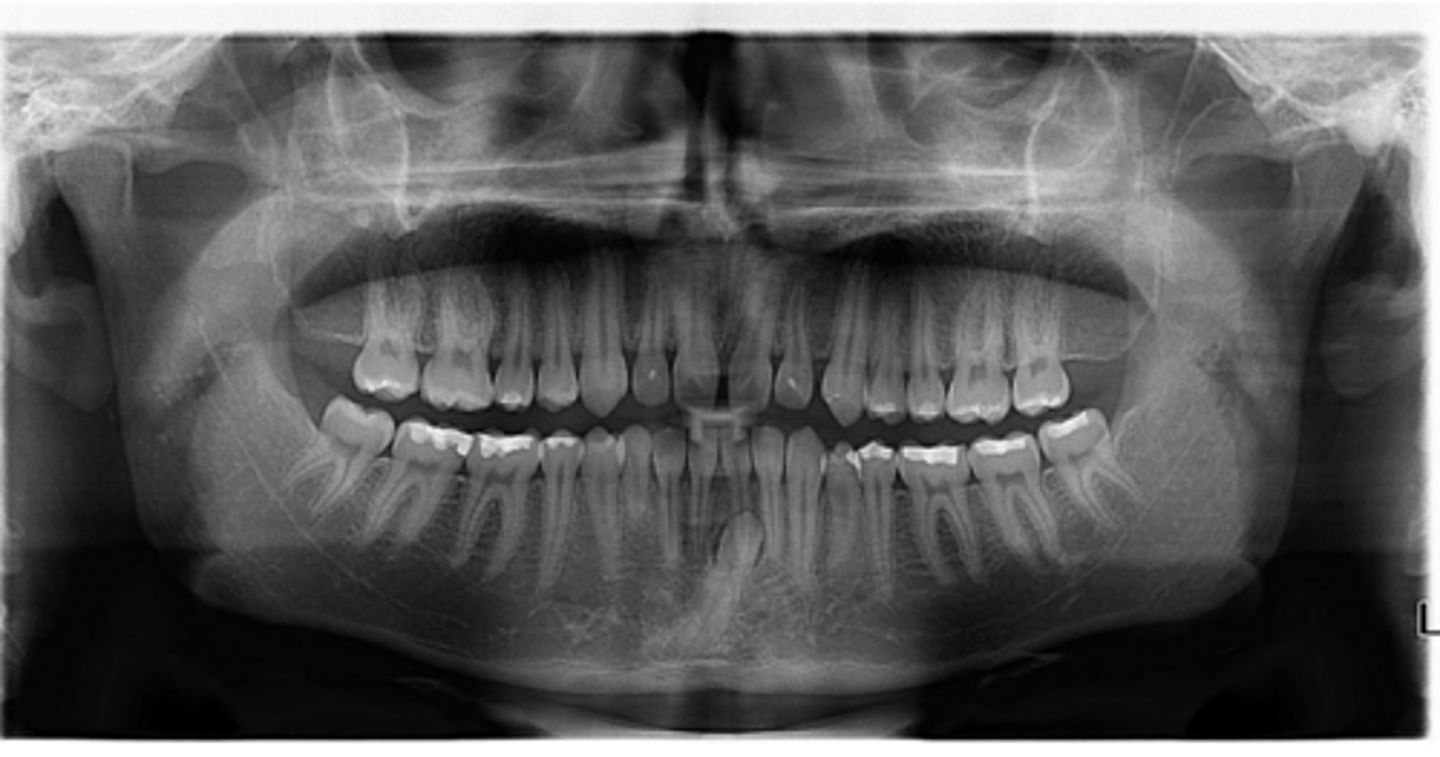

Right primary canine

Are there retained primary teeth?

Yes

Are there any impacted teeth?

Are the condyles symmetrical?

Is there a dilacerated root?

No

The mandibular left side has normal premolar/canine eruption, but the rigth side is abnormal.

Is the eruption pattern of this patient normal or not?

Are there any supernumerary teeth?

Are there any retained primary teeth?

Not at this stage

Are there impacted teeth?

Yes, within the range of normal

Symmetric condyles?

Yes - maxillary first molar

Dilacerated roots?

Yes - laterals

Are there congentially missing teeth in the maxillary arch?

Yes - an incisor

Are there congenitally missing teeth in the mandibular arch?